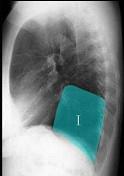

问题 如图所示正常胸部X线影像图像上,该英文字母所代表的肺段为 ( )

选项 A.内基底段 B.前基底段 C.外基底段 D.后基底段 E.背段

答案 D